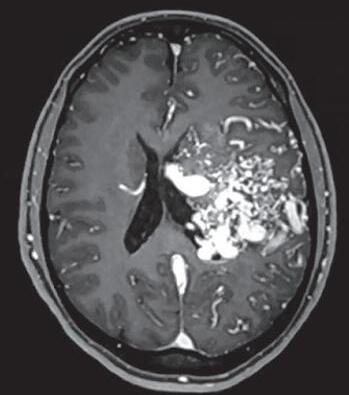

Fig. 1-16. RNM encéfalo T1 com contraste: (a) Coronal e (b) axial demonstrando MAV grau 4 frontoparietal esquerda. (c,d) Arteriografia cerebral AP mostrando a irrigação pelos ramos da cerebral anterior e média esquerda, além da cerebral anterior direita, com drenagem superficial para o seio sagital superior. Seta azul apontando para o nidus da MAV.